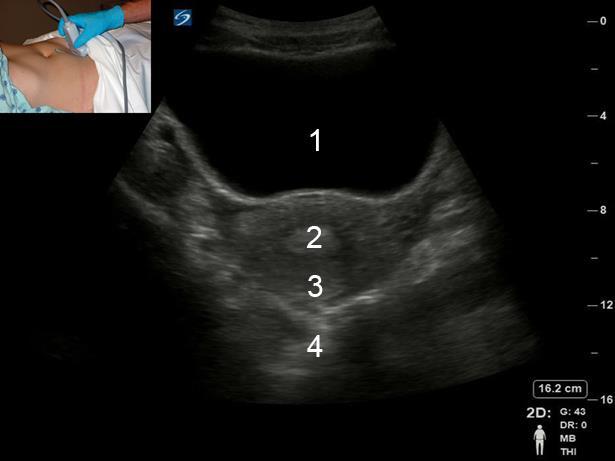

Pelvic Transverse Uterus Sweep Image

Bladder

Endometrium

Uterus

Posterior Cul-de-sac